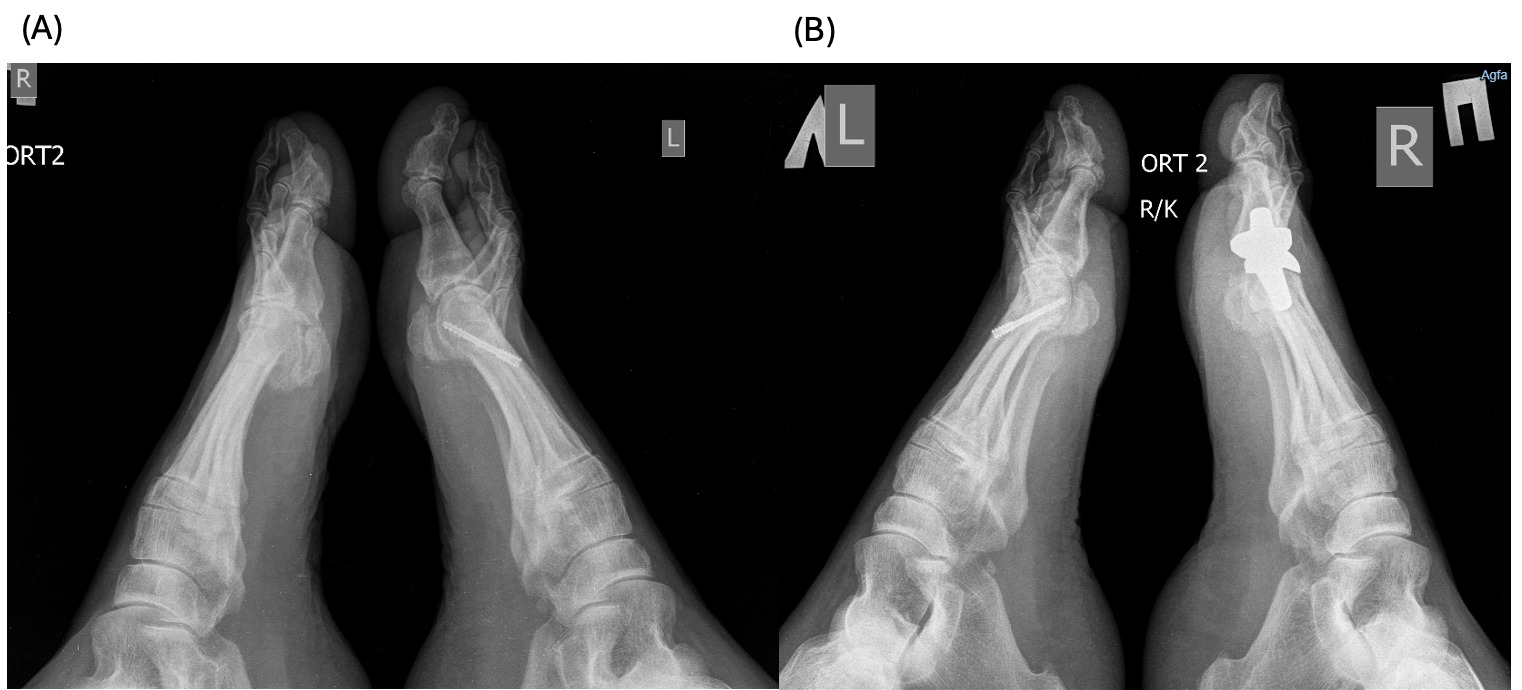

A 61-year-old female patient with a history of trauma on the left first MTP presented to the clinic with complaints of pain and limited range of motion of the right foot first MTP for the last several years. The patient was receiving conservative treatment within the last year with temporary relief; therefore, the surgical intervention was recommended and the patient was referred to our clinic. Physical examination revealed almost no movement and pain on palpation, as it can be seen on Figure 1 (A).

After the total first MTP replacement using ceramic implant, 2 and 6 months later, there is preserved improvement in the joint mobility, absence of pain and discomfort during movement (Figure 1 (B, C)). The patient reports satisfaction with the use of joints.

The patients had undergone radiographic evaluation of the MTP joint before the surgery, right after surgery, and 2 and 6 months after surgery (Figures 4-9). The radiographic imaging after the surgery confirmed the correct positioning and alignment. At the follow-up, the radiographic images were done to analyze the early healing process, to observe if there were any signs of implant loosening. 2 months after the surgery, no patient had periprosthetic radiolucencies, no stress-related changes. 6 months after surgery, no osteolysis, no migration of the implant.

This case series demonstrates successful short-term results following total first metatarsophalangeal (MTP) joint replacement using ceramic implants in patients with hallux rigidus. All three patients presented significant improvement in AOFAS scores within 2 months postoperatively, with preserved improvement at 6 months. Notably, Patient C, who had the lowest preoperative score (27/100), achieved the greatest relative improvement, reaching 92/100 at 2 months and 89/100 at 6 months. These functional outcomes were confirmed by physical examination findings, with clear improvements in joint alignment and reduction in deformity (Figure 1-3, (B, C)). Moreover, radiographic imaging revealed no signs of complications such as implant loosening, migration or stress-related changes.